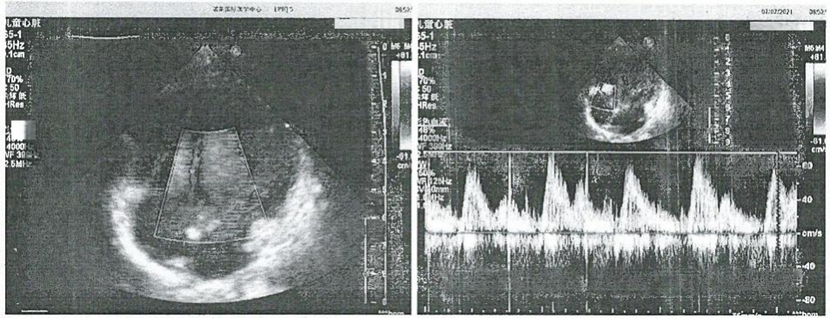

入院时已完成相关术前检查。常规血常规、肝肾功能检查、凝血功能、胸部X光片和超声心动图检查未显示异常或手术禁忌症。 2021年7月5日,患者接受机器人辅助立体定向脑外科手术。术后头部CT扫描示无明显出血,定位准确。患者安全返回病房。术后常规静脉输液、氧疗及心电图监测。治疗期间未出现并发症及不良反应。